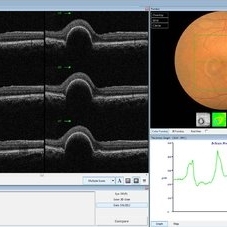

Best Disease Best DiseaseMar 9 2013 by Hamid Ahmadieh, MD OCT of the right eye of a 49-year-old man with decreased VA due to advanced Best disease. Photographer: Soodabeh Fooladin, Negah Eye Center, Tehran Imaging device: Heidelberg Spectralis Condition/keywords: Best disease, optical coherence tomography (OCT)